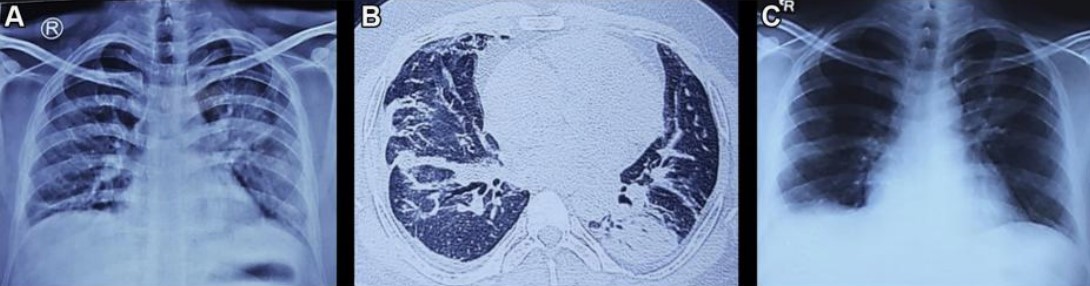

圖2 A.患者入院時(shí)的胸片;B.入院后行胸部CT掃描;C.患者出院時(shí)的胸片